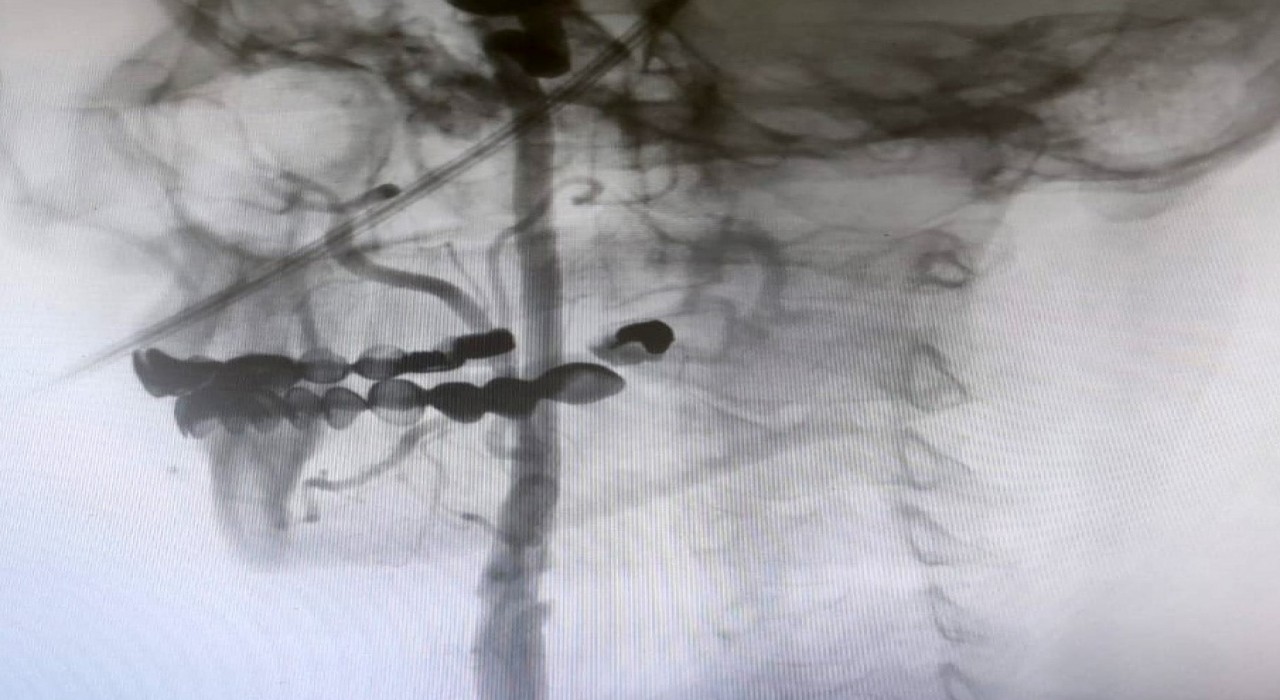

Manisa Şehir Hastanesi’nde, beyin damarlarındaki tıkanıklıklara karşı ameliyatsız stent yöntemi başarıyla uygulanıyor. Uzmanlar, şah damarındaki daralmaların inme riskini büyük ölçüde artırdığını vurgularken, bu modern yöntem sayesinde hastaların ertesi gün taburcu olabildiğine dikkat çekti.

Manisa Şehir Hastanesi’nde girişimsel nöroloji ve girişimsel kardiyoloji uzmanlarının iş birliğiyle, beyni besleyen en büyük damarlar olan karotis (şah) damarlarındaki tıkanıklıklara karşı modern tedavi yöntemleri başarıyla uygulanıyor. Uzmanlar, bu damarlarda gelişen ciddi darlıkların inme (felç) riskini önemli ölçüde artırdığını belirtiyor. Bu nedenle, felç riskini azaltmak amacıyla hastalara stentleme işlemi uygulanıyor.

Girişimsel Nöroloji Uzmanı Doç. Dr. Ezgi Sezer Eryıldız, "Beynimizi besleyen en büyük damarlar karotis damarları yani şah damarlarıdır. Eğer bu damarlarda ciddi bir darlık olursa inme yani felç geçirme riski belirgin şekilde artmaktadır ve bu riski azaltmak için stentleme işlemi uygulanmaktadır. Rutin olarak hastalarımız bu açıdan değerlendiriliyor ve bu işlemi uyguluyoruz" dedi.

"Boyun damarlarını açma işlemi iki şekilde yapılabilir. Bir karotis endarterektomi dediğimiz ameliyatla bir diğer yöntem ise perkutan girişim dediğimiz stent yöntemiyle açılabilir. Biz kliniğimizde nöroloji ve kardiyoloji olarak bir konsey yapıyoruz. Damarı ciddi tıkalı olan ve buna bağlı felç geçirmiş hastalarda bu konseyde hastaya işlem yapıp yapmama kararı veriyoruz. Verdiğimiz karar çerçevesinde eğer hastaya işlem kararı vermişsek femoral arter dediğimiz kasık arterinden bir şitle 6 ya da 7 F çapında bir şitle ince bir boruyla bu damara giriş yapıyoruz ve boyun damarlarına ulaşıyoruz. Özellikle teller, filtreler ve stentlerle bu damarları açıp hastanın tedavisini gerçekleştiriyoruz. İşlem ameliyatsız olduğu için hastamız ertesi gün rahat bir şekilde problem olmazsa işlemde taburcu olabiliyor bu işlemden sonra. Bu işlemin yapılması için özellikle anjiografinin olduğu girişimsel nöroloji uzmanının ve girişimsel kardiyoloji uzmanının olduğu ve bu konuda yeterli vaka tecrübesine ve deneyime sahip uzmanların olduğu merkezler gerekir. Bunu yapabilmek için belli bir vaka sayısına ulaşmak ve bu konuda tecrübeli olmak gerekiyor. Biz de Manisa Şehir Hastanesi’ndeki girişimsel kardiyoloji ve nöroloji uzmanları olarak bu işlemi kliniğimizde efektif bir şekilde gerçekleştiriyoruz."